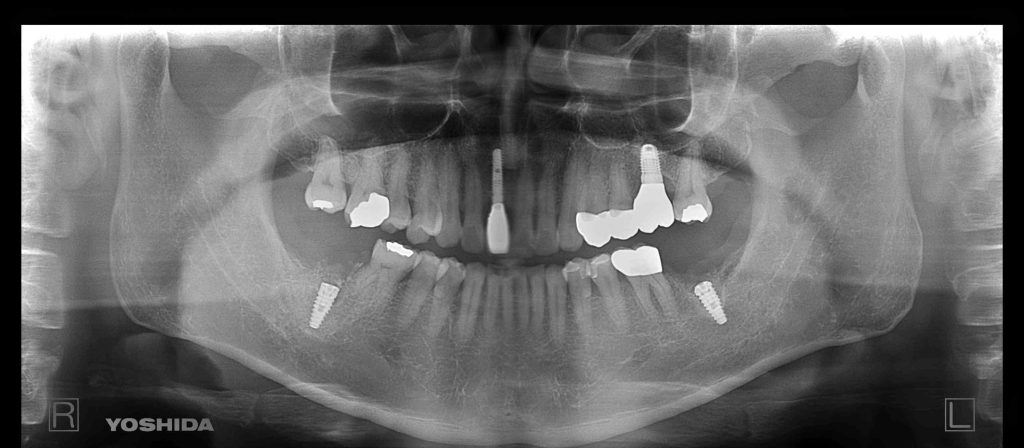

根本的な原因は咬合に起因しており、歯周病が進行して抜歯が必要な状態でした。

神経に近いケースなので抜歯と同時に炎症組織をしっかり取り除きCTで確認しながら初期固定がしっかりとれるインプラントデザインを選択することで、3ヶ月後には骨結合が得られると思います。

費用 1本あたり

抜歯即時インプラント埋入 385000円

GBR 55000円

仮歯 33000円

ジルコニアクラウン 176000円